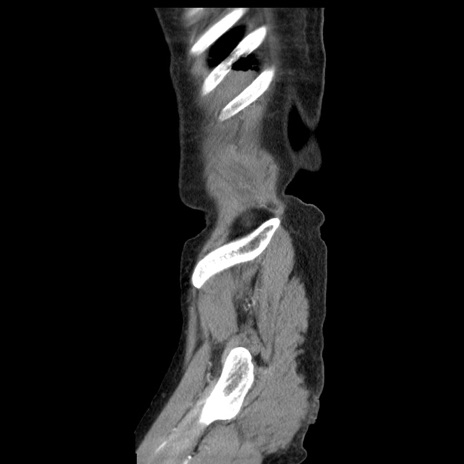

症例1(矢状断像)

【症例】80歳代女性

【主訴】腹痛

【現病歴】8時間前から腹痛あり来院。

【既往歴】糖尿病、脂質異常症、子宮体癌にて子宮全摘術

【身体所見】意識清明・会話良好だが腹痛で苦悶様、全腹部にわたって反跳痛と圧痛あり

【データ】WBC 13600、CRP 0.14、LDH 224、CK 90